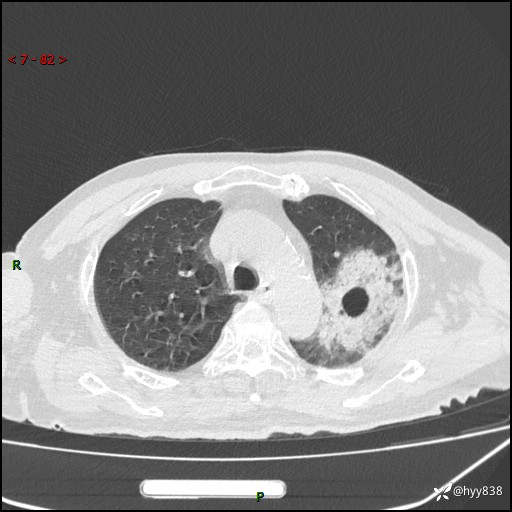

胸部CT平扫(2024.7.24)